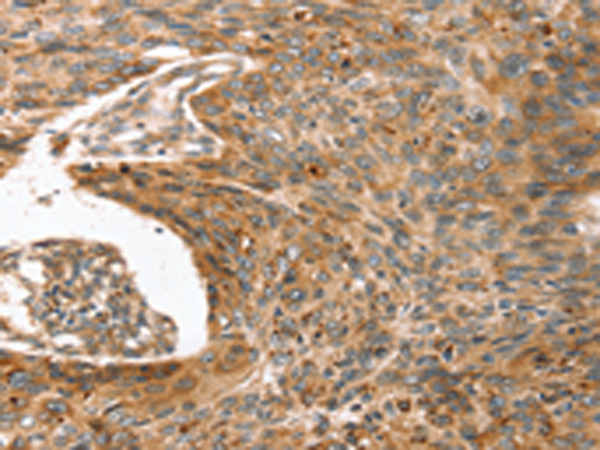

IHC positive control: |

Human esophagus cancer |

IHC Recommend dilution: |

25-100 |